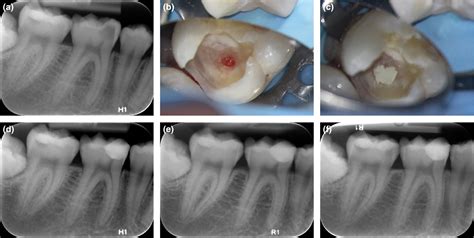

When a dentist evaluates tooth pulp exposed, they will look for the viability of the nerve. Depending on the severity of the damage, the treatment plan will vary. Below is a summary of the most common professional interventions.

Condition Severity Primary Treatment Goal

Mild Exposure (Small) Direct Pulp Capping To protect the pulp and encourage healing.

Moderate Decay Root Canal Therapy To remove infected tissue and save the tooth.

Severe Damage/Fracture Tooth Extraction To prevent infection from spreading.

When you visit the dentist, they will likely take X-rays to assess the extent of the damage. If the pulp is inflamed but not yet necrotic (dead), the dentist might attempt to save the pulp through a process known as pulp capping, where a biocompatible material is placed over the exposed area to seal it off. If the pulp is already infected, a root canal is the standard of care to remove the bacteria, disinfect the chamber, and restore the structure of the tooth.